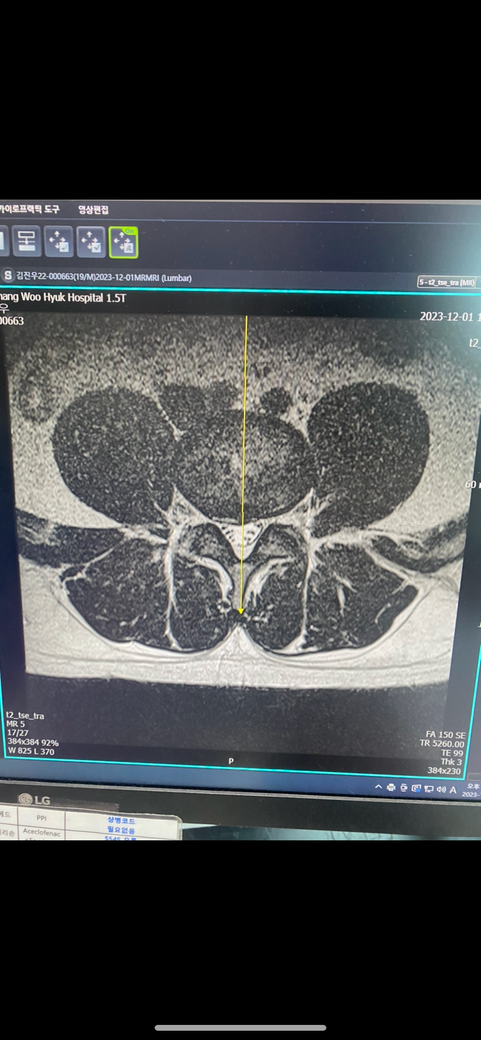

안녕하세요 5년전부너 허리디스크로 많이 힘들었습니다 진단서 아무것조 안떼고 mri 사진으로 3급현역판정을 받았습니다 제 지금 상태는 4개월전 mri사진인데 저때보다 지금 방사통과 허리통증으로 너무 힘듭니다 재검시 공익가능성이 있나요? 허리 상태가 지금 너무 안좋아서 걱정입니다